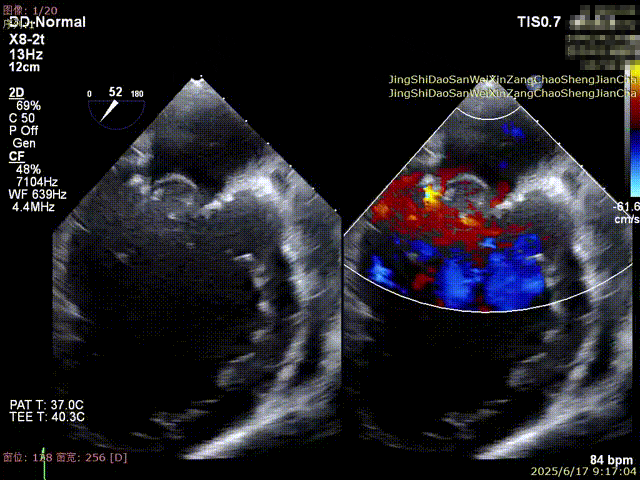

全麻后,首先在心前区的肋间切开3-4CM小切口,暴露心脏的心尖位置,心尖穿刺后进入导丝,利用导丝交换导管鞘完成通路建立。将系统送入左心房,顺利到达二尖瓣病变区域。在经食道超声引导下,术者通过反复评估二尖瓣反流位置、抓捕位置、反流程度,在2区主动脉瓣与二尖瓣闭合线垂直进行巧妙夹合,最终植入一枚ValveClamp®MVC-Ⅲf夹。超声评估夹子固定良好,组织桥完整,无葫芦征,位置、轴向均符合预期。患者术后反流程度从大量转至少量,手术取得圆满成功。患者恢复良好,已经顺利出院。

捕获瓣叶,进行夹合 3D切面调整位置及钟向

反流得到明显改善 术后3D动图